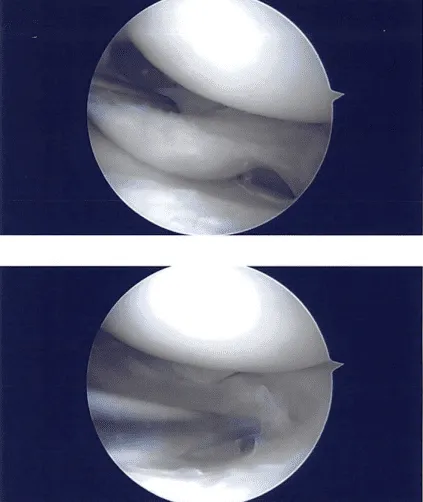

El examen del compartimento lateral mostró desgarros del menisco lateral y se presentaban suturas. El menisco lateral se desbridó con el uso de mordedor hacia arriba, mordidor recto y afeitador. Se realizó un desbridamiento exhaustivo. Había cierta cantidad de artritis en el cartílago tibial.

Se lograron márgenes equilibrados. Casi el 40% del menisco lateral fue resecado en el procedimiento para lograr márgenes equilibrados. Se tomaron y guardaron las fotos finales. El examen del compartimento no mostró artritis. Se tomaron y guardaron las fotos finales. La rodilla fue completamente irrigada y drenada.

Imágenes intraoperatorias